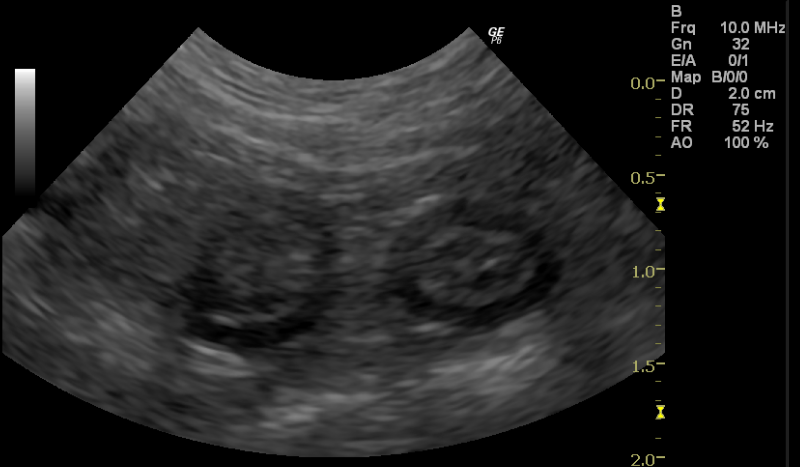

猫の消化器型高分化型リンパ腫。

高齢のねこちゃんで多い胃腸のリンパ腫。特にこの高分化型リンパ腫ではお薬の治療で長期にがんを抑えて普通の生活を送れることが多いです。

case.1

雑種猫、9歳齢、不妊雌。慢性の下痢、体重減少。組織生検にて高分化型リンパ腫の診断。

chlorambucil、predonisoneの内服治療。

症状消失、長期寛解生存。